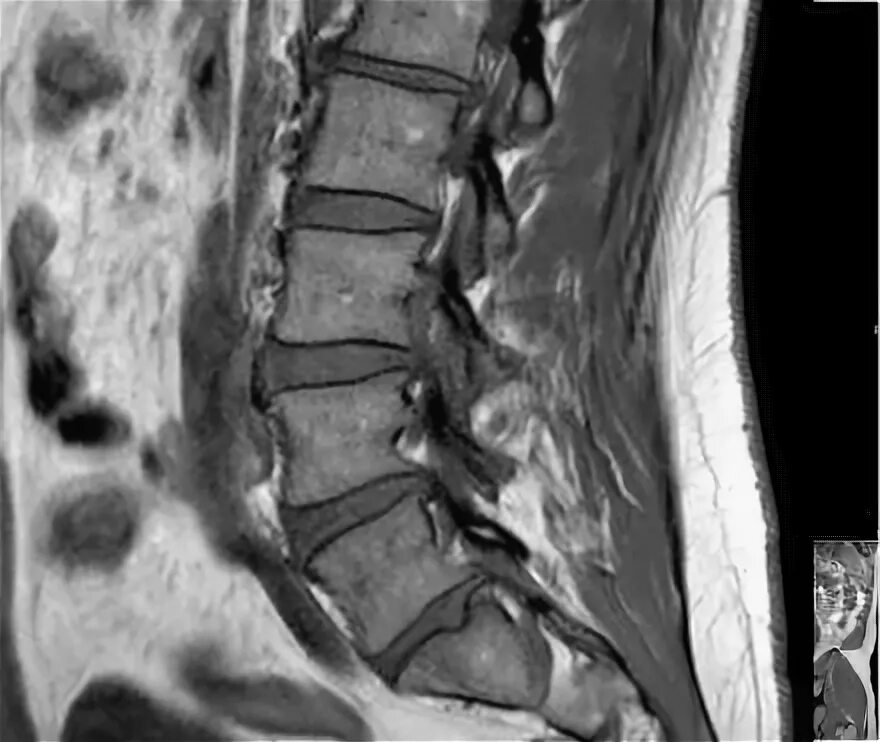

Грыжи дисков с3 с7